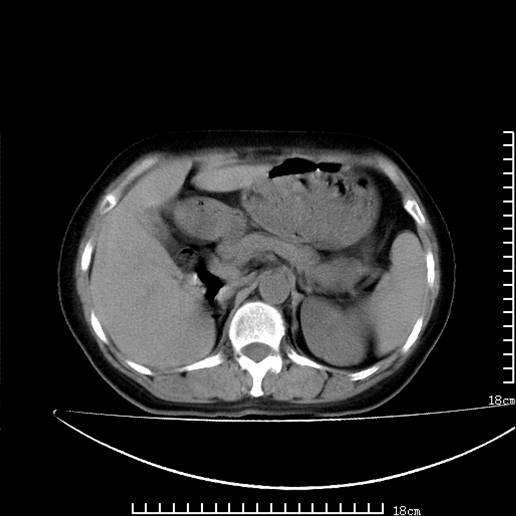

以下是引用pujunzhi在2008-5-30 15:31:00的发言:[br]异位肾—盆腔肾。当看到肾窝无肾脏时,要想到孤立肾和异位肾,异位肾最常见是盆腔肾,偶见胸腔,易误认为肺占位,只要想到就不会漏诊。建议增强扫描。